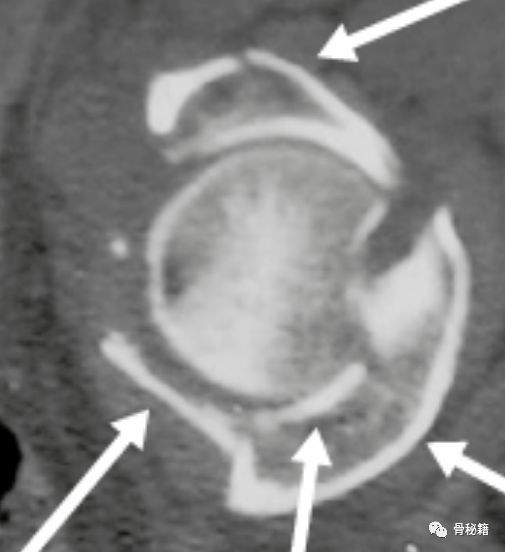

术前的CT和X线都是很好的工具,通过影像学来分辨臼顶到底有没有压缩,压缩了多少。

CT图像可以更好的分辨是否压缩还有压缩的数值,还有具体的方位,是前方 还是后方?内侧还是外侧?